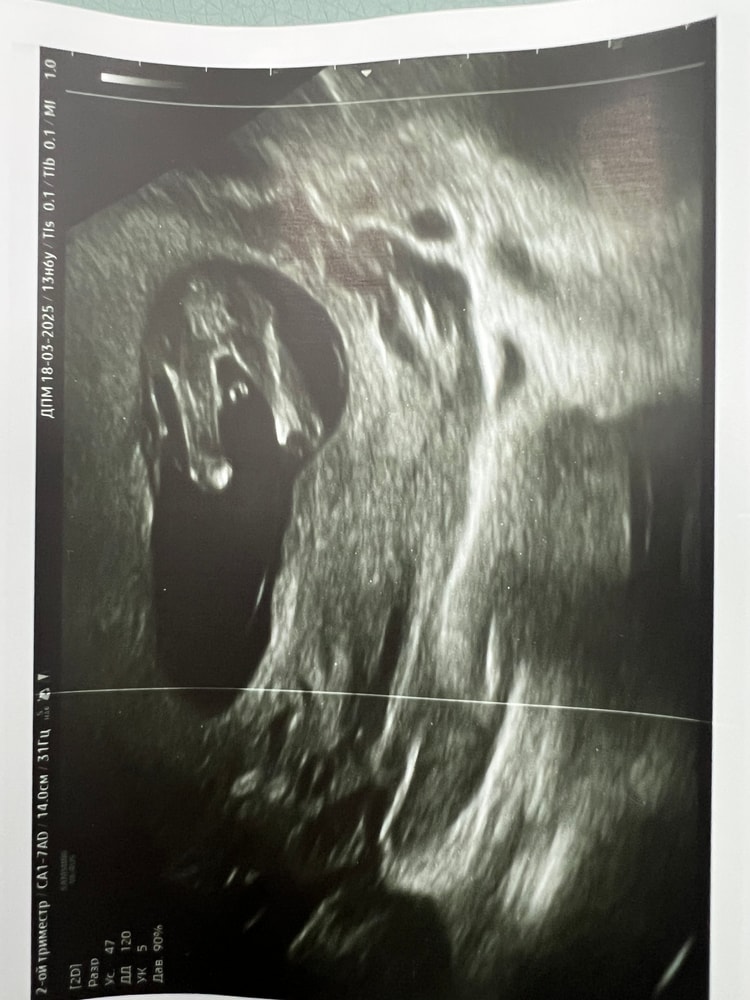

Сегодня ходили с мужем на УЗИ по определению пола.

Врач сначала сказала, что девочка, потом в другом ракурсе сказала мальчик, потом снова повернула и сказала «Давайте остановимся на девочке» 😄 Как мне кажется, на фото прямо конкретная девочка. Муж смотрел в экран, говорит очень активная, крутится, вертится, пинается 🥹

Подтвердился ли под на 2 скрининге ?

Лёля, здравствуйте тоже была в "Здоровая я" на этом УЗИ. Пол подтвердился на 21 неделе, делала в "Клинике Капачинской". Там на большом телевизоре с мужем рассматривали)